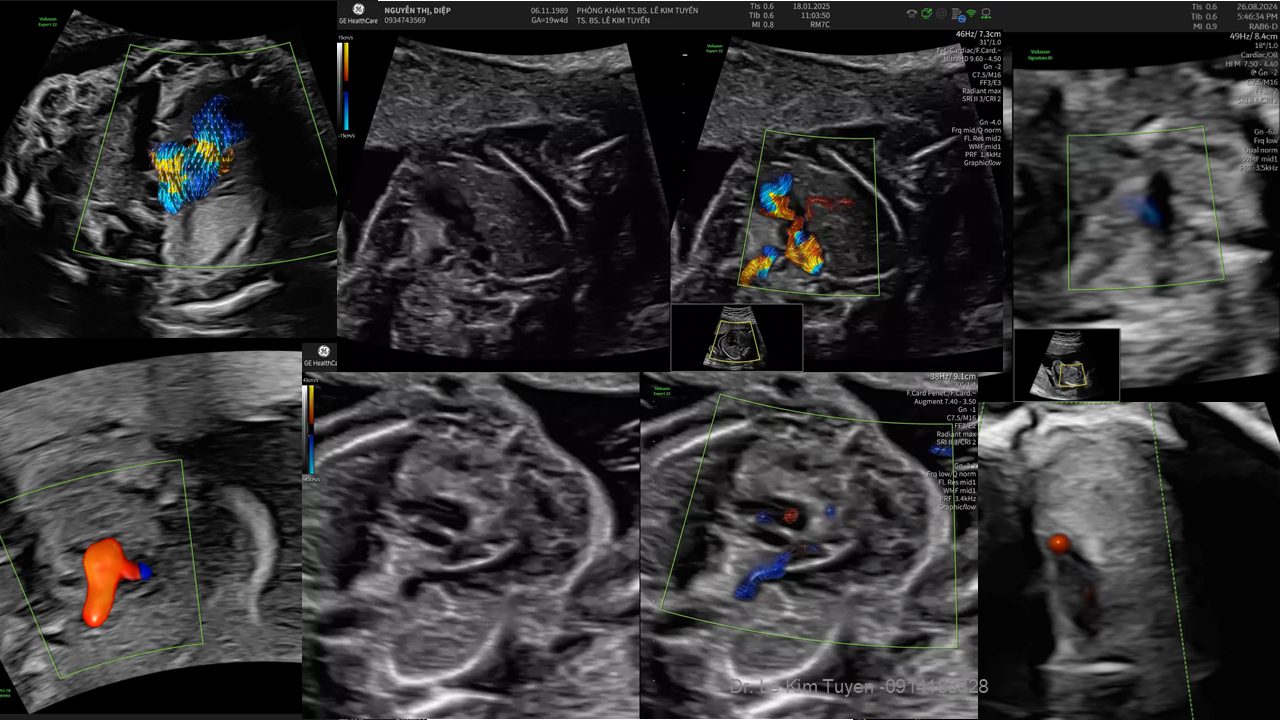

Áp dụng công nghệ Graphicflow trong phát hiện bệnh tim bẩm sinh cần cấp cứu sơ sinh

TS. BS. Lê Kim Tuyến

Bệnh viện Tim Tâm Đức